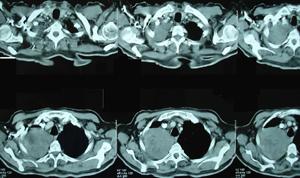

Εικόνα 3α-δ

Αξονική τομογραφία θώρακος σε διαφορετικά επίπεδα. Μάζα μαλακών μορίων που καταλαμβάνει το μεγαλύτερο μέρος του άνω λοβού. Η μάζα πιέζει την πνευμονική αρτηρία, τον κύριο βρόγχο και την άνω κοίλη φλέβα και πρόκειται για μάζα εκ μαλακών μορίων με νεκρώσεις κατά περιοχές.

Α-Β

Γ-Δ